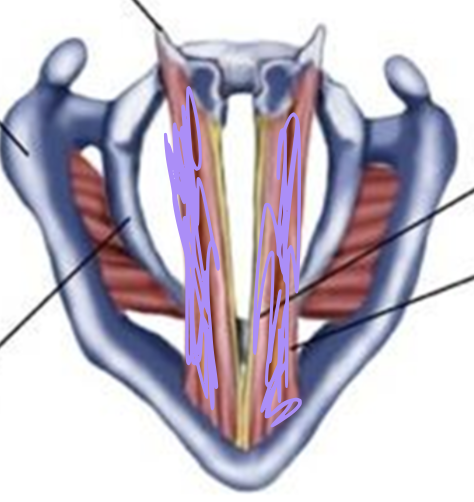

What is this muscle?

Thyrovocalis (tense VF, pitch up)